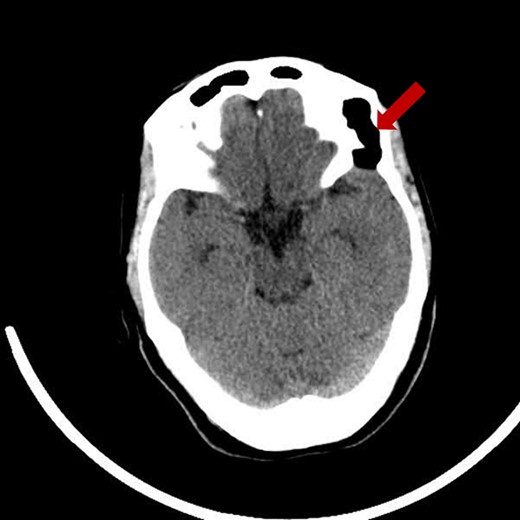

Prior diagnostic imaging included a computed tomography (CT) scan, revealing a hypodense lesion in the left fronto-zygomatic region (Fig. 1). Subsequent brain magnetic resonance imaging (MRI) showed a high-intensity lesion on T1-weighted images (T1WI) (Fig. 2A), and an iso-to-hyperintense lesion on T2-weighted images (T2WI) (Fig. 2B).

Pre-operative axial CT scan displaying a well-defined, low attenuating lesion in the left fronto-zygomatic region.